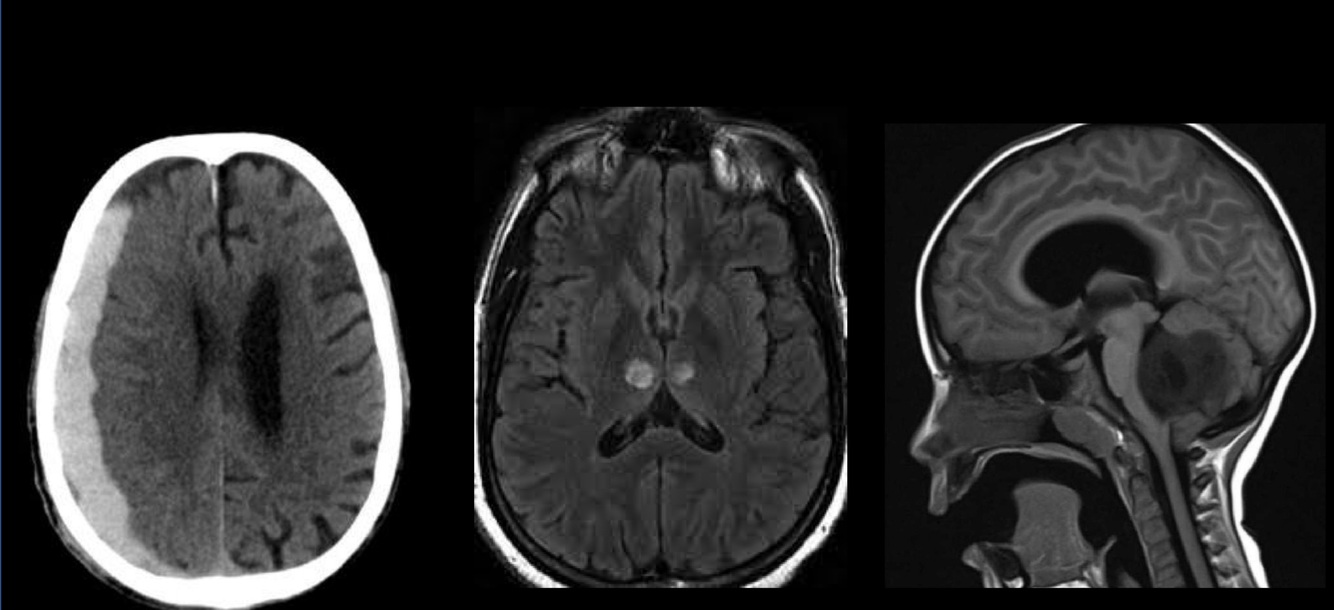

Las dos primeras son supratentoriales y la última infratentorial.

Las obstrucción de la arteria de Percherón ocurre en talamos y causa COMA.